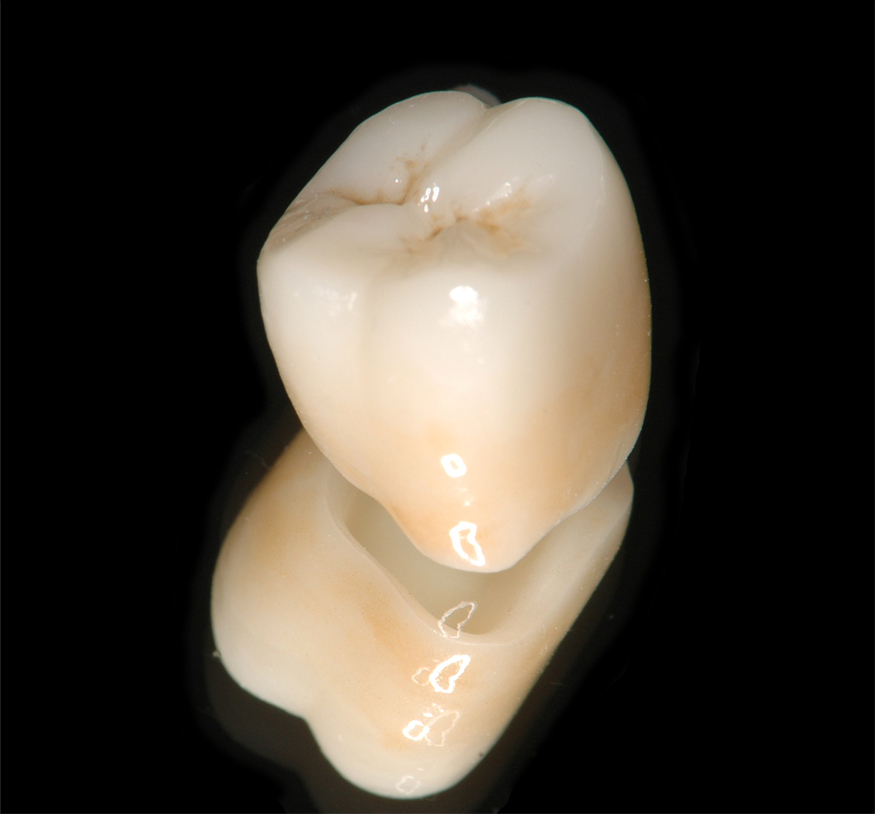

ジルコニア・クラウンの治療例

患者さんは古い金属のかぶせ物の色を気にして来院しました。

①右上第一大臼歯にジルコニア(強化セラミック)クラウンをセットしました。

ジルコニア・クラウンの治療例

患者さんは古い金属のかぶせ物の色を気にして来院しました。

①右上第一大臼歯にジルコニア(強化セラミック)クラウンをセットしました。